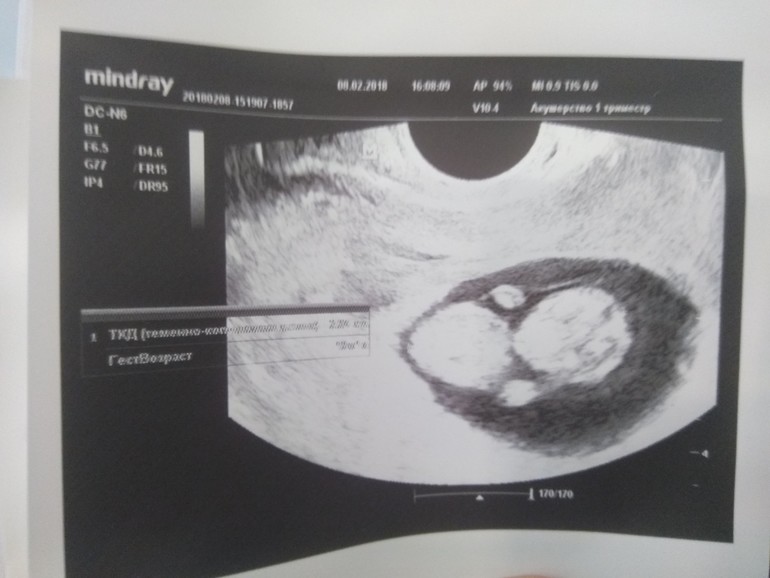

Так началась наша история в 9 счастливых месяцев. Беременность проходила очень легко, хотя и была я с того самого момента на утрожестане. Первое УЗИ, второе и третье показывали замечательные результаты.

На первом узи пообещали мальчика, назвали заранее Илюшкой. Но в 18 недель пол моего мальчика оказался девочкой, поэтому ждали мы оставшийся срок Анечку.